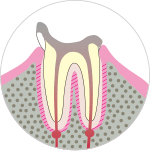

段階.C4

穴が広がり、歯がほとんどない状態。歯根だけが残ります。

神経(歯髄)が死んで腐敗し、膿みが出ることで口臭が強くなります。

歯根の先や周囲にまで炎症がおよび、歯茎の中の骨が溶けて、さらに痛みが起こり熱が出ることもあります。

主な症状

- ・大きな穴があく

- ・ズキズキと刺すような痛み

- ・膿

- ・歯が割れる

治療法

- ・ブリッジ(固定式入れ歯)

- ・義歯(取り外し式入れ歯)

- ・インプラント